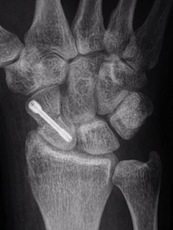

Bei der Operation kann der Hautschnitt auf der Beuge- oder Streckseite des Handgelenks erforderlich sein. Die Bruchenden werden unter Sicht aufeinander gestellt. Die Knochenstabilisierung erfolgt mit einer Titanschraube, die in das Kahnbein vollständig versenkt werden kann. In seltenen Fällen, bei eingestauchten Brüchen, muss Knochenmaterial, z.B. aus der Speiche, in den Bruchspalt eingebracht werden. Anschließend ist eine Gipsruhigstellung ist für ca. 2-6 Wochen zu empfehlen. Die Entfernung der Schraube ist nur in Ausnahmefällen nötig. Neben regelmäßigen Kontrollen der Wund- und Hautverhältnisse sind zur Überwachung der Bruchheilung Röntgenkontrollen anzufertigen, gegebenenfalls auch eine Computertomographie.

Versorgung eines Kahnbeinbruches mit einer Titanschraube, die im Knochen versenkt wird.

Ausheilung des Bruches